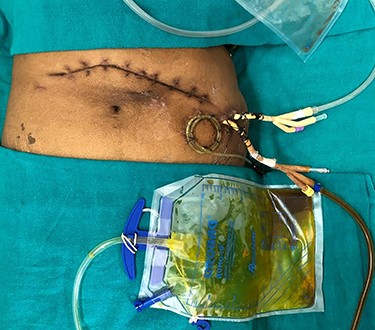

An 81-year-old female, a known case of idiopathic acute necrotizing pancreatitis, had been on percutaneous catheter drainage (PCD) for infected pancreatic necrosis at 6 weeks of onset (Fig. 1). On the eight day, she required a second PCD insertion for persistent lesser sac collection and sepsis. During PCD intervention, there was active bleeding from the catheter site which led to emergency pancreatic necrosectomy, hemostasis from the bleeding gastrocolic ligament vessel, closed lesser sac drainage and feeding jejunostomy. After surgery, she did well and was discharged on Day 15. The lesser sac drain output was clear with a raised amylase level. On the 24th day after surgery, she was readmitted for the high (300 ml/day) bilious drain output (Fig. 2). She denied any fever, vomiting or abdominal pain. She was hemodynamically stable without abdominal distention or tenderness. Her blood investigations revealed leukocytosis (13 600 cells per cubic milliliter), but normal renal function tests and serum chemistry. A diagnosis of the duodenal fistula was presumed and was kept nil per oral, intravenous fluids, antibiotics and initiation of feeding jejunostomy. She was doing well for the next 1 week with a good appetite. Contrast computed tomography (CT) excluded any peripancreatic collections, and importantly there was no oral contrast extravasation in the para-duodenal region. The drain output was persistently high (300–350 ml/day) and bilious with normal fluid amylase activity. We requested for fistulogram, which surprisingly revealed an external biliary fistula from the distal common bile duct (Fig. 3). Endoscopic retrograde cholangiopancreatography (ERCP) and bile duct stenting (7Fr × 10 cm double pigtail plastic stent) was performed, which led to the closure of the fistula over the next 7 days. At a 6-month follow-up, the patient is doing well.

Imaging showing post-pancreatic necrosectomy status with bile leak in the lesser sac drain.